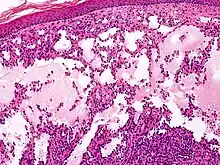

Proliferating lymphangioma, H&E stain. Sometimes endothelial cells begin to divide excessively.

Microscopically, the vesicles in lymphangioma circumscriptum are greatly dilated lymph channels that cause the papillary dermis to expand. They may be associated with acanthosis and hyperkeratosis. There are many channels in the upper dermis which often extend to the subcutis (the deeper layer of the dermis, containing mostly fat and connective tissue). The deeper vessels have large calibers with thick walls which contain smooth muscle. The lumen is filled with lymphatic fluid, but often contains red blood cells, lymphocytes, macrophages, and neutrophils. The channels are lined with flat endothelial cells. The interstitium has many lymphoid cells and shows evidence of fibroplasia (the formation of fibrous tissue). Nodules (A small mass of tissue or aggregation of cells) in cavernous lymphangioma are large, irregular channels in the reticular dermis and subcutaneous tissue that are lined by a single layer of endothelial cells. Also an incomplete layer of smooth muscle also lines the walls of these channels. The stroma consists of loose connective tissue with a lot of inflammatory cells. These tumors usually penetrate muscle. Cystic hygroma is indistinguishable from cavernous lymphangiomas on histology.[4]